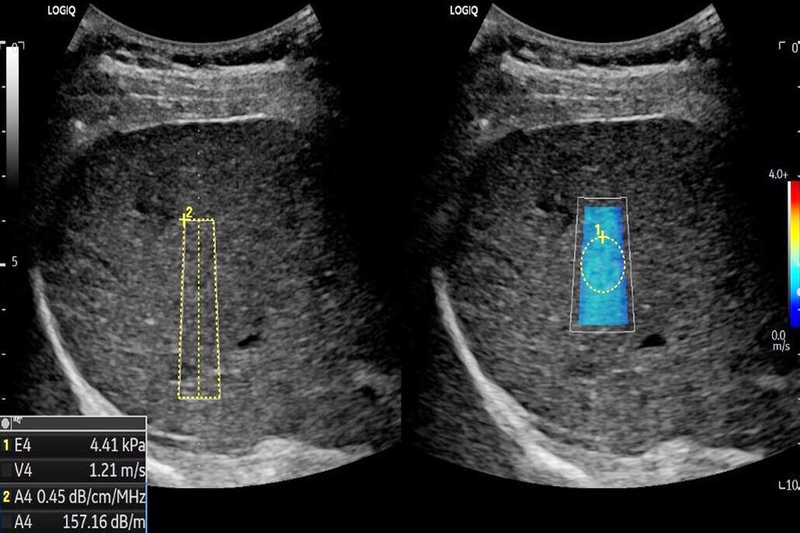

Hiện tượng giãn bể thận thai nhi, hay còn được gọi là thận ứ nước, xảy ra ở khoảng 1% số trường hợp thai nhi (với tỷ lệ nam cao hơn nữ). Siêu âm được sử dụng để đo đường kính trước và sau bể thận thai nhi, và kết quả này sẽ phụ thuộc vào tuổi thai để chẩn đoán tình trạng giãn bể thận.

Nếu đường kính trước và sau bể thận vượt qua mức ≥ 10mm ở thai kỳ trên 20 tuần, được coi là thận ứ nước và cần tiến hành khảo sát xem có giãn các đài thận hay không.